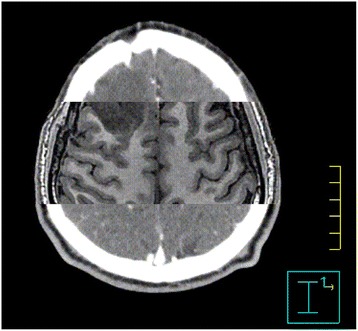

The fused fMRI activation maps and the white matter tracts overlaid on the anatomical MRI volume were exported as separate grayscale dicom images and loaded onto Pinnacle planning system software version 9.2 (Philips Medical Systems, Netherlands). The anatomical MRI images were registered with the CT volume for each patient. Figure 1 shows the anatomical MRI images were registered with the corresponding axial CT planes for a glioma case.

Figure 1.

T1-weighted MR imaging and the corresponding axial CT after registration.